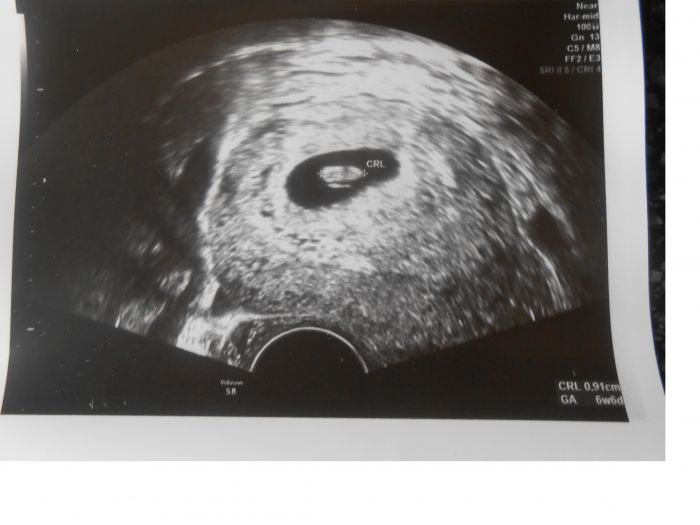

Ahoj holky, přidávám se taky mezi dubňátka. Včera jsem byla na ultrazvuku, jsem 7+2 (TP 2.4.) a vše vypadá v pořádku. Snad to bude i nadále bez problému, jako moje první těhotenství. Máme doma chlapečka, co před týdnem oslavil 2. narozeniny. Když jsem ho čekala, seznámila jsem se tu na diskuzi s holkama a do dneška si píšeme a s mnohýma se i vídáme, což je super

Holky, při prvním těhu jsem poměrně hodně krvácela v 5tt a vše bylo v pořádku (nejspíš nějaké opožděné implantační krvácení) a nyní taky v 6tt špinění a dle UZ je všechno dobré. Nepanikařte!

Přidávám fotečku z UZ